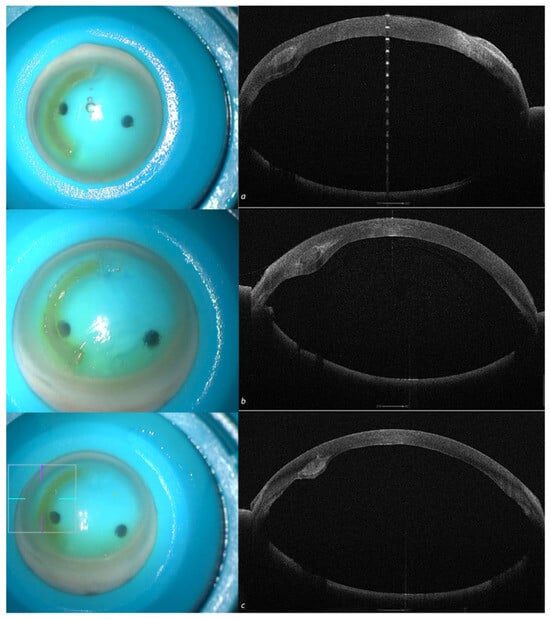

2.3.1. Patient 1: Single ACXL CAIRS Implant

| Parameter | Preoperative | Postoperative |

|---|---|---|

| MPP 3 mm | 45.32 D | 44.30 D |

| SimK (K steep) | 53.53 D | 49.89 D |

| Astigmatism | −7.25 D@25° | −3.71 D@30° |

| Coma Aberrations | 1.49 D eq. @90 | 0.19 D @165° |

| Thinnest Point (µm) | 362 | 378 |